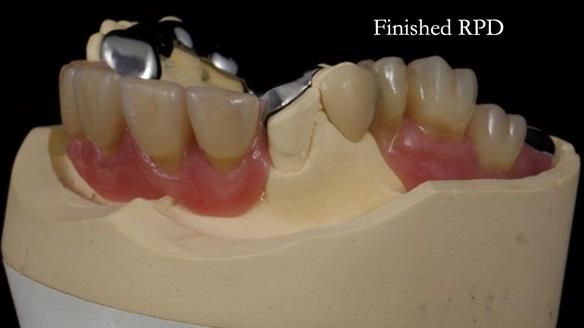

Keith’s combat denture case study

Keith’s case was one of the most challenging and rewarding cases I’ve treated this year. This 64 year old man presented with ill-fitting acrylic partial dentures that lacked stability, retention, and aesthetics. They constantly broke. He had lost the upper front teeth in a road traffic accident in his early 20s. The unopposed teeth had erupted, taking up space. After careful planning, we made a durable, metal-based upper partial denture/splint to address his dental concerns. He loved the outcome.

1. Denture design: A custom cobalt-chromium framework was Scandinavian-designed to maximise stability, protect the remaining teeth, and allow for future additions if needed.

Keith’s denture incorporated a Duracetal shell clasp on upper right first premolar (Myerson), which are designed to be virtually visible, providing a more aesthetic solution while enhancing patient comfort. The Scandinavian-inspired approach, based in modern removable prosthodontic techniques, ensured the denture was not only durable but also visually pleasing. Additionally, the design was carefully planned to allow for future modifications, ensuring that if Keith loses additional teeth, the denture can be adapted rather than replaced entirely.

I also used the Dahl concept to re-establish the occlusion upon fitting the RPD, which helped to intrude the lower left canine without needing to grind it too much.